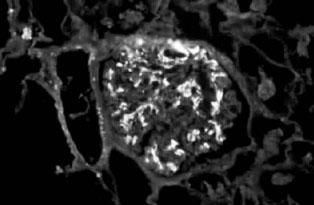

IgA肾病的典型病理表现为:在光镜下常见系膜细胞增生、基质增多(图2—10),常呈局灶节段性分布。IgA肾病轻微者则只有轻微系膜增生,亦可呈弥漫增生(常有局灶节段性加重)。约20%病例可出现新月体,通常不超过肾小球的30%。IgA肾病进行性病例可见球囊基底膜变形、裂解;肾小球基底膜“溶解”。免疫荧光镜下,可看见在肾小球系膜中呈弥漫分布的颗粒或团块状IgA沉积物(主要是IgA1(图2—11)。60%~90%的IgA肾病病例伴C3和IgG沉积,但强度较弱。IgA轻链以λ为主,有J链,无分泌块,通常无C1q和C3沉积。电镜下几乎都可见到细小均一的颗粒状电子致密物,分布于系膜区;若在上皮下或内皮下出现,则可判断为IgA肾病病情严重。上皮细胞足突则常常是正常的。

图2—10 系膜增生性IgA肾病,肾小球系膜细胞和基质增生(PAS x200)

图2—11 IgA肾病,IgA呈团块状沉积于系膜区(免疫荧光 x400)